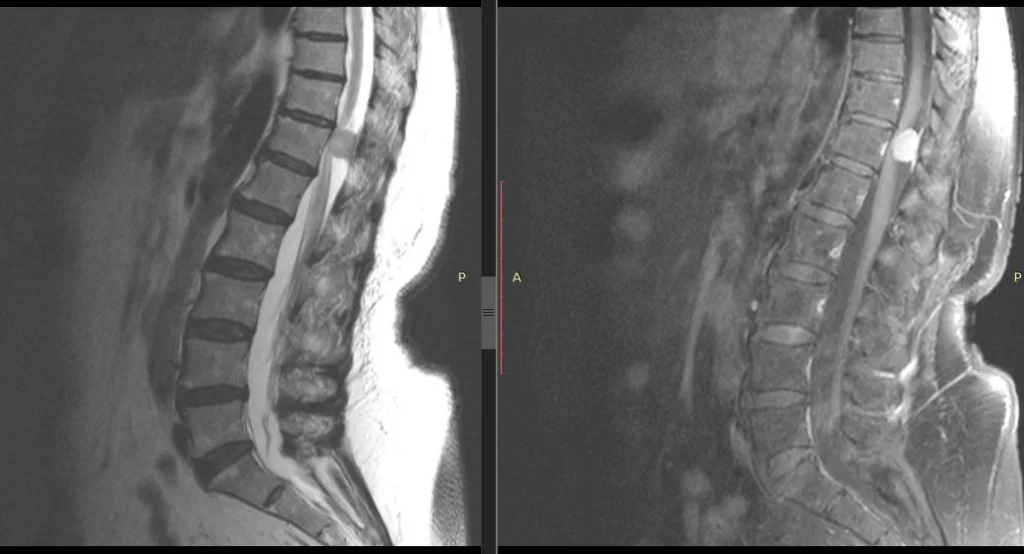

Μηνιγγίωμα Σπονδυλικής Στήλης (Θ12 σπονδύλου)- Πεταλοπλαστική, ολική αφαίρεση

Ασθενής γυναίκα 66 ετών η οποία αρχικά παρουσίασε ζωστηροειδές άλγος οσφύος και στη συνέχεια αδυναμία βάδισης. Ο έλεγχος με μαγνητική τομογραφία με σκιαγραφικό ανέδειξε μηνιγγίωμα